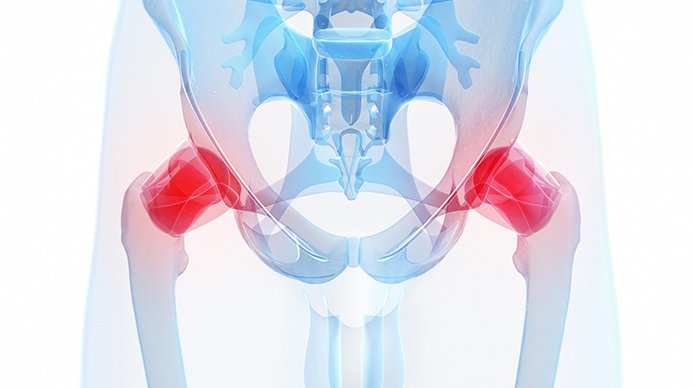

고관절은 흔히 엉덩이 관절이라고 불리며, 골반 쪽에 위치한 공-소켓(ball-and-socket) 형태의 관절입니다. 둥근 모양의 대퇴골두가 오목한 비구(acetabulum)에 맞물려 있어 골반과 허벅지를 연결하는 역할을 합니다.

이 관절은 체중을 지탱하고 보행, 달리기 같은 다리의 움직임을 가능하게 하는 핵심 구조입니다.